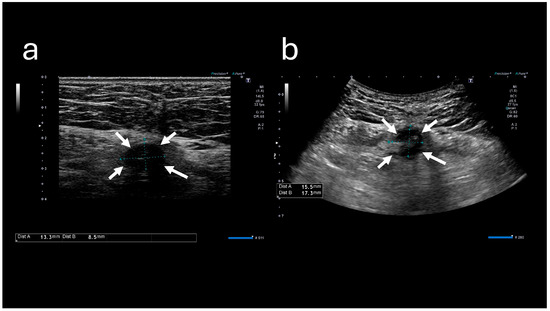

The A-US and A-CT findings suggested the enlargement of the abscess below the umbilicus. Enhanced A-CT revealed multilocular abscesses (Figure 4 and Figure 5). The abscess was drained with the patient under sedation, with local anesthesia administered as follows: intravenous midazolam (3 mg), intravenous pentazocine (15 mg), and subcutaneous injection of lidocaine (8 mg). When the base of the umbilicus was opened with mosquito forceps, a large amount of purulent discharge was observed (Figure 6). The umbilicus was carefully washed, and a drainage tube was inserted at its base. The Gram stain of the pus showed a multi-bacterial pattern including Gram-positive cocci, Gram-positive rods, and Gram-negative rods (Figure 7). He was hospitalized at our hospital, and the oral antibiotic was changed to intravenous ampicillin/sulbactam (3 g every 8 h).

Figure 4. Abdominal ultrasound sonography images. (a) Image obtained at the time of initial visit. (b) Image obtained at the time of the second visit. The low-echoic lesion (indicated by arrows) appears enlarged.

Figure 5. Abdominal computed tomography images. (a) Image obtained at the time of initial visit. (b) Image obtained at the time of the second visit. The soft tissue lesion below the umbilicus (indicated by arrows) appears enlarged. (c) Contrast-enhanced image demonstrates a multicapsulated soft tissue lesion.